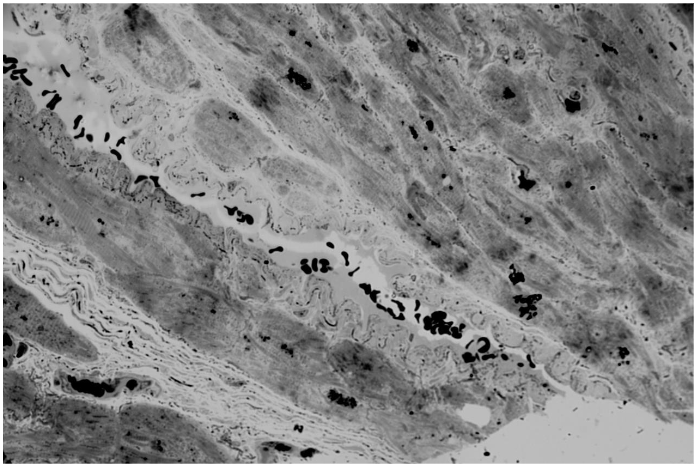

Cardiomyocytes are not wide in transverse diameter. Interstitial edema is expressed. Microcirculatory bed vessels vary in profile lumen width and wall thickness. The vessel wall is unevenly thickened, especially in large arterioles. Opposite walls merge and form bridges that unevenly block the profile lumen in several areas. Closure of opposite walls in a large arteriole leads to the formation of a new profile lumen in the vessel wall. And also closure of opposite walls of a large arteriole leads to the formation of a convolute consisting of forming chambers with the presence of erythrocytes in the lumen of the chambers. Such a convolute fences off part of the arteriole from the general lumen. On the pathological growth scale 3 points.

The closure of opposite walls in a large arteriole leads to the formation of a new lumen of the profile in the vessel wall. And also the closure of opposite walls of a large arteriole leads to the formation of a convolute consisting of forming chambers with the presence of erythrocytes in the lumen of the chambers. Such a convolute fences off part of the arteriole from the general lumen. On the scale of pathological growth 3 scopes.

Cardiomyocytes are different in width with prevalence of thicker ones. Walls of small arterioles are slightly thickened. Large arterioles with pronounced thickening of the walls and their numerous invaginations into the lumen of the vessel profile are presented. Takes place formation of bridges in such vessels. It is interesting to observe a very large arteriole of unusual configuration, having two separate large lumen profiles and invaginations of the walls into these lumens. And also taking place closure of opposite walls of the arteriole and the presence of an isolated lumen in the wall of the arteriole. This patient has a small arteriole that has formed a convolute of several chambers. And also, there are small arterioles De Novo located close to each other. On the scale of pathological growth from 3 to 4 points.

Cardiomyocytes vary in diameter, many are wider. Proliferation of connective tissue between cardiomyocytes. Interstitial edema. Arterioles vary in profile size from large to medium and small. Large arterioles with unevenly thickened walls as well proliferation of cellular elements of the vessel wall are observed. Large arterioles have a pronounced process of invagination of opposite walls into the profile lumen. Bridges are formed in the profile lumen of large arterioles, sometimes in large quantities. Small arterioles are also characterized by the presence of a bridge and the formation of two profile lumens. Several profile lumens are formed in a large arteriole in the vessel wall, which indicates the presence of a convolute. According to the pathological growth scale, 3 points.

Ischemic heart disease is a rather insidious disease. A significant role here is played by atherosclerotic damage to both the coronary main vessels and the primary link of the microcirculatory system, the arterioles. The main resistance vessels of coronary arteries are arterioles (with a diameter of <200 mk) and play a key role in the physiological regulation of myocardial reperfusion. The regulatory mechanisms of arterioles can be further divided into large arterioles (100-200 mk that mediate dilation), medium arterioles (40-100 mk), and small arterioles (less than 40 mk). The studies we conducted on atherosclerosis of arterioles in men of different ages visualized more or less the same changes, while the assessment scores varied from 3 points in one patient to between 3 and 4 in 3 patients. The visualization of the biopsy from patient 1 indicates that this is a relatively young heart. The patient is 46 years old. There is no hypertension in the cardiomyocytes and no proliferation of myofibrils. Ischemic heart disease reveals atherosclerotic arterioles. There is pathological growth of the intussusception type. Characteristic invagination into the lumen of the arterioles and the formation of bridges take place. Unlike the first patient, who had a slight wall thickness, the three others showed changes in wall thickness of varying degrees of severity. This is also a negative factor in atherosclerosis of arterioles.

The increase in diameter and thickening of the walls of arterioles during atherosclerosis occurs due to the proliferation of cellular elements, where smooth muscle cells play a very important role. While under physiological conditions, during reperfusion, arterioles can change the sizes of their luminal diameters, in ischemic disease, the growth factor plays a significant role. The increase in the diameter of arterioles occurs up to a certain limit, after which further changes occur in the manner of intussusception. The number of arterioles involved in this process is significant, whether they are large with a diseased diameter or small. This determines what arterioles can subsequently form De Novo. At the same time, the formation of bridges is also a negative process, as it can obstruct normal blood flow. Four patients are characterized by the presence of formed or forming convolutis. This is also a negative point, as it leads to a violation of blood flow. The term convolutes means multi-chambered, similar to the capillaries of the brain in hypertension. We can assess the visualization of atherosclerotic arterioles on a 5-point scale of pathological growth in the manner of intussusception. The term of intussusception angiogenesis, arteriogenesis is indicate the ways of new capillaries arteries and venous formation from previous.